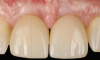

Fig 15. Clinical comparison of the volumetric gain obtained with the intervention, frontal views. Fig 15: Frontal view at baseline. Fig 16: Frontal view at 1-year post-treatment.

Figure 15

Fig 16. Clinical comparison of the volumetric gain obtained with the intervention, frontal views. Fig 15: Frontal view at baseline. Fig 16: Frontal view at 1-year post-treatment.

Figure 16